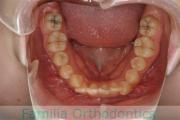

上顎

下顎